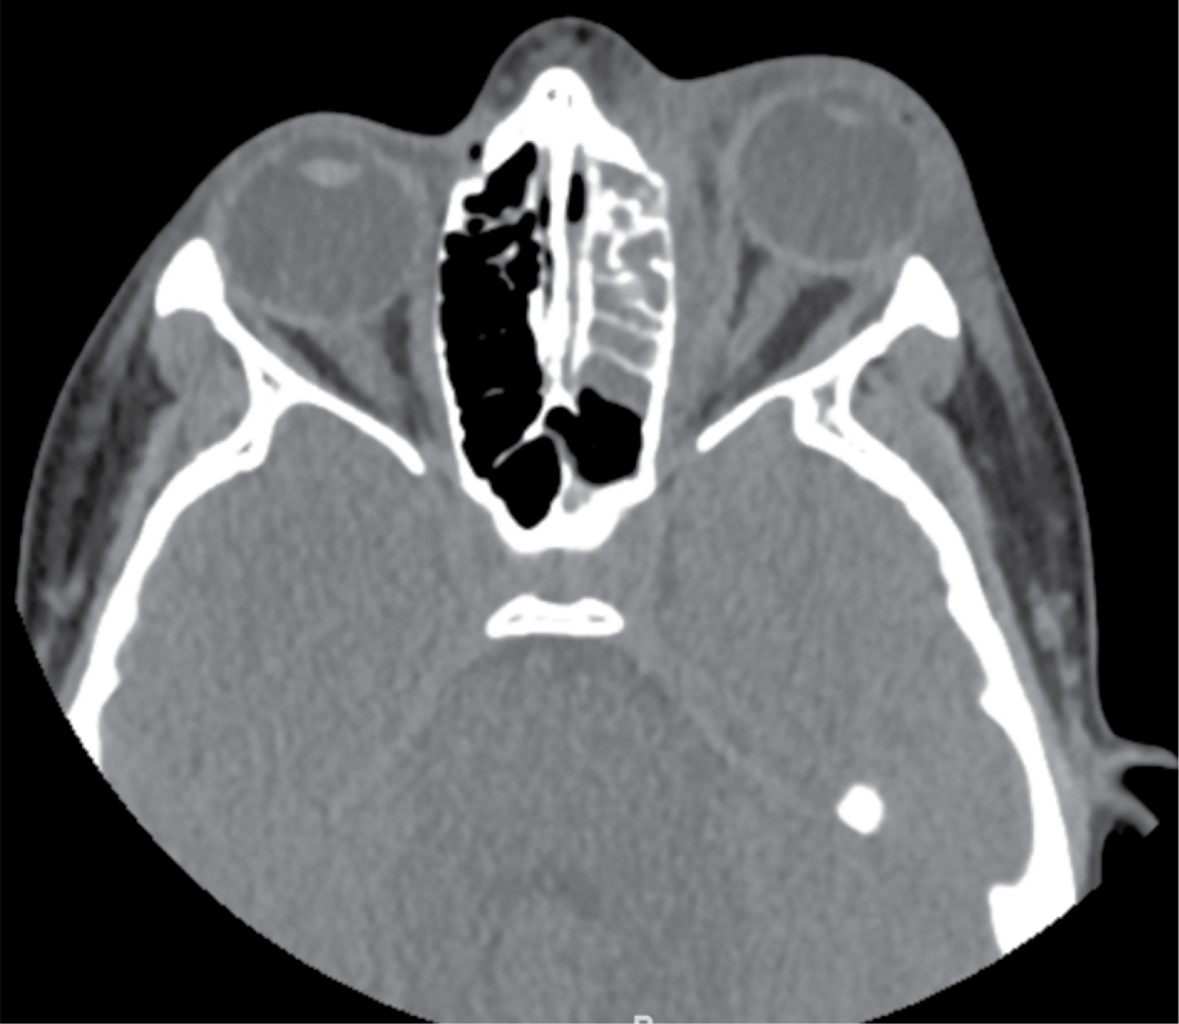

Orbital cellulitis secondary to sinusitis due to Prevotella loescheii

Orbital cellulitis is a potentially serious entity characterized by the presence of proptosis, ocular pain, limitation of ocular movements and decreased visual acuity. Given the location of the infection and the possibility of sequelae, early and intensive management is essential. In the following article we describe a case of an 13-year-old adolescent who presented with orbital cellulitis secondary to sinusitis due to Prevotella loescheii. He required intravenous antibiotherapy and surgical intervention for drainage, with good clinical evolution.

Figure 1